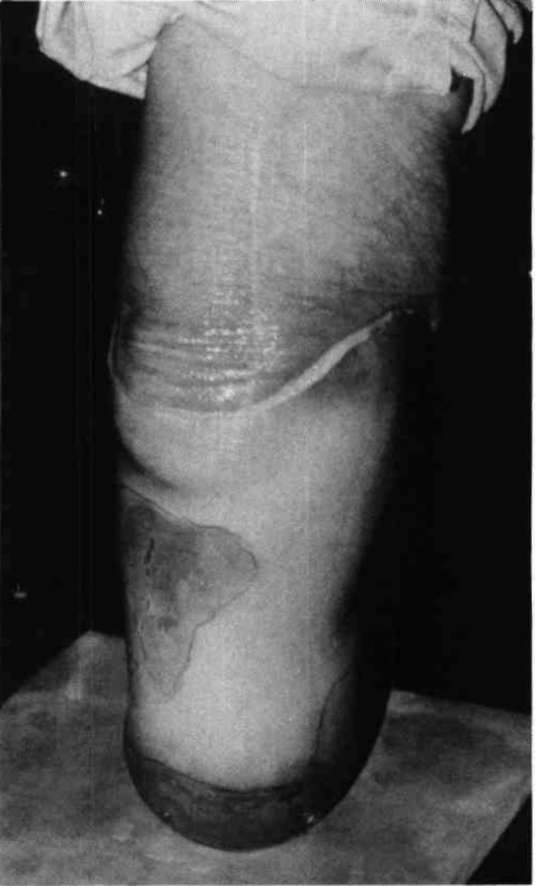

Figure 1. A transparent socket is vacuum-formed over a plaster cast that has been modified in the usual manner.Lubrication of the stump with petroleum jelly, or equivalent lubricant, is necessary for donning the check socket when it is used without a prosthetic sock. The patient then stands bearing weight in the test socket, which rests on a platform or stand that can be adjusted in height so that weight-bearing is the same on each side and the pelvis is level (Fig. 2). While the patient continues to stand, the stump in the transparent socket is evaluated by identifying changes in skin color. Blanching, or even whiteness, indicates that the pressure levels are acceptable. Excessive shiny blanching indicates increased pressure, which is perhaps excessive. Redness indicates voids or lack of total contact. If a patient complains of too much pressure when an area is surrounded by red, then algina-tion should provide relief by establishing total contact. If the patient complains of too much pressure when an area is surrounded by white and blanching, relief is provided by spot heating and stretching the socket in the area of complaint. A thin flat probe, like a corset stay, is often useful for specifically locating pressure areas for purging small pockets of trapped air, or gauging skin tensions within the socket (Fig. 3).

Figure 2. The patient bears one half of his weight in the transparent socket for evaluation of fit by the prosthetist observing the color of the skinFigure 3. Evaluation of fit by observation can be augmented by use of a flat slender probe.